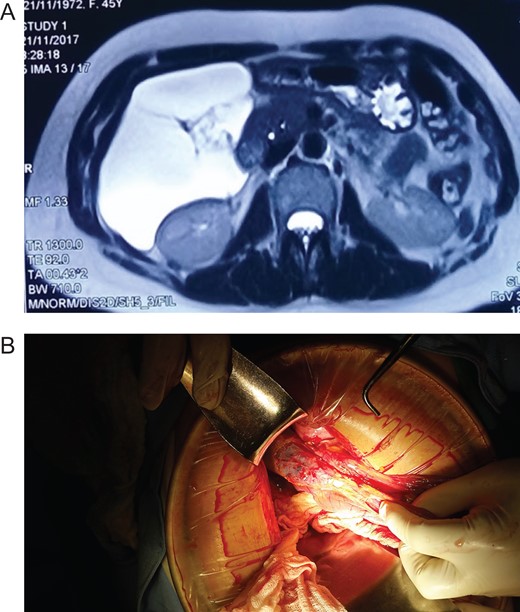

Patient is a 45-year-old female patient, with past medical history of gastritis. Six months before she sought medical attention, she was complaining of mild upper abdominal pain, however, due to her previous condition she was medicated with proton pump inhibitors assuming that the pain was due to her gastritis. In the last 3 months, she noticed a mass in her upper abdomen and the pain became more severe and started to affect her daily activities, thus she presented to a routine physical exam. No weight loss or other constitutional symptoms were noticed. Also no history of malignancy in her family was mentioned. On clinical examination, a 12 × 15 cm2 mass was discovered on her upper abdomen, mild pain was found on palpation but no tenderness was present. An abdominal ultrasonography revealed a 15 × 15 cm2 septate thin-walled giant cystic mass, it was anechoic and had a volume of ~735 ml. The cyst occupied most of the hepatorenal space and it was in intimate contact with the liver, right kidney and pancreas (Fig. 1A). Due to the size of the mass, CT was requested, it revealed well-defined 19.7 × 15 × 10 cm3 giant cyst, the cyst was located within the small bowel mesentery and it was in intimate contact with the liver, gallbladder, pancreas and right kidney (Fig. 2A). Nevertheless, the tomography could not rule out that the mass had some sort of communication with the bile duct or the pancreas. This is why a magnetic resonance cholangiopancreatography found that the cyst was attached but had no communication with the bile duct or the pancreas (Fig. 3A). CBC and blood work was normal.

(A) CT revealing a well-defined 19.7 × 15 × 10 cm3 giant cyst. (B) Giant cyst surrounded by the bowel. (C) Pathology, cyst wall covered by adipose tissue. (Hematoxylin and eosin staining 40×.)

Due to the size of the cyst and clinical condition surgery was planned. At laparotomy, a 19 × 15 × 10 cm3 mesenteric cyst was discovered (Fig. 1B), the cyst was near the root of the small bowel mesentery but did not compromise its main vessels, it had a yellowish appearance (Fig. 2B), and clear fluid was found within the cyst. Multiple adhesion were identified between the cyst wall and the transverse colon, liver, third portion of the duodenum and gallbladder. With these findings surgery was straightforward, complete resection of the cystic mass was performed, however, the cyst wall was completely attached to the body of the gallbladder and could not be resected without compromising it (Fig. 3B), so a cholecystectomy was performed as well. After this, the remainder of the procedure continued without any complication.

Pathology reported a giant primary mesenteric cyst, it was lined with a single layer of cuboidal epithelial cells and partially covered by adipose tissue and prominent vasculature, it had a yellowish wall and its thickness varied between 0.1 and 0.3 cm (Fig. 1C). Its interior had a white trabecular internal surface with brown patches it did not have any communication with other organs, and no areas of malignancy were found (Fig. 2C).